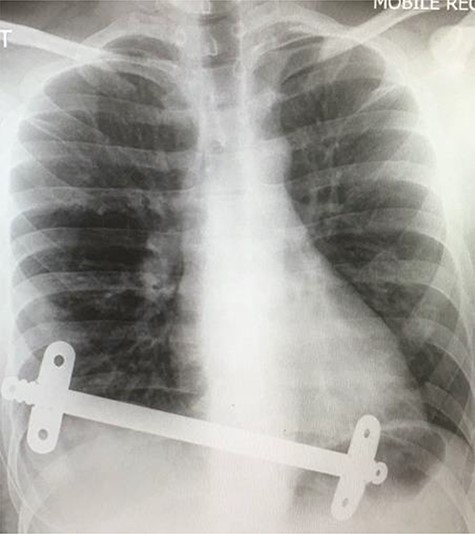

Chest X-ray taken after the removal of the upper substernal bar. The second bar is seen, traversing the diaphragm, having migrated into the stomach.

Our patient was followed up annually. After two and half years, he developed a right-sided wound infection, initially treated with antibiotics. It was decided to remove the bar for prevention of recurrent infection. The chest X-ray showed migration of the lower-placed bar (Fig. 2). The upper bar and associated stabilizers were removed through the bilateral small incisions without any complication; however, the lower bar was not palpable. Therefore, a left-side thoracotomy was performed; however, the bar was not found in the chest. The incision was extended to a midline laparotomy (Fig. 3). This revealed an erosion of the bar in to the stomach after passing over the left lobe of the liver (Fig. 4). The bar and stabilizers were completely removed, and the hole in the stomach was closed directly with sutures. The patient was discharged home without any further complication after successful recovery.